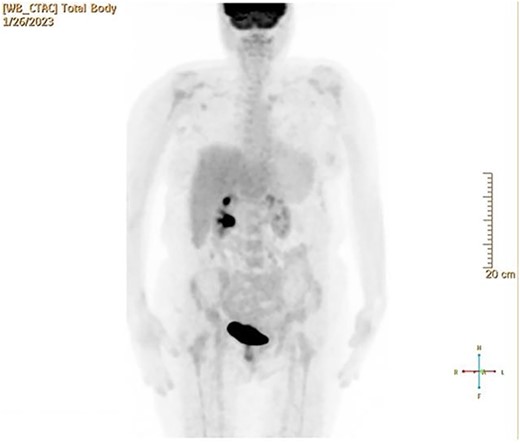

CT and PET scans revealed multiple positive lymph nodes, but metastatic lesions were not found in chest, abdominal organs, or bone (Fig. 2). Genetic and molecular tests revealed wild rat associated sarcoma, wild BRAF, proficient MMR, and negative HER-2. Tumor markers were positive. The patient started chemotherapy, which included CAPOX, cetuximab, and FOLFOX. PET scan was done for re-evaluation, and marked partial disease response was observed with currently no evidence of disease. After that, the patient started to experience reversible amnesia, bizarre behavior followed by right side upper limb weakness, hyperreflexia on the right side, positive Babinski sign on the left, and positive Hoffman sign bilaterally. Brain MRI was done, which revealed a left fronto-parietal extra-axial space-occupying lesion with vasogenic edema and midline shift (Fig. 3). Patient underwent brain lesion resection through left fronto-parietal craniotomy. The pathology revealed GBM (Fig. 4). IHC stain of neoplastic cells showed wild IDH and positive for GFAP, and 30% of the neoplastic cells showed positive for Ki67.

PET scan revealed multiple positive lymph nodes but no metastatic lesions in chest or abdominal organs or bone.